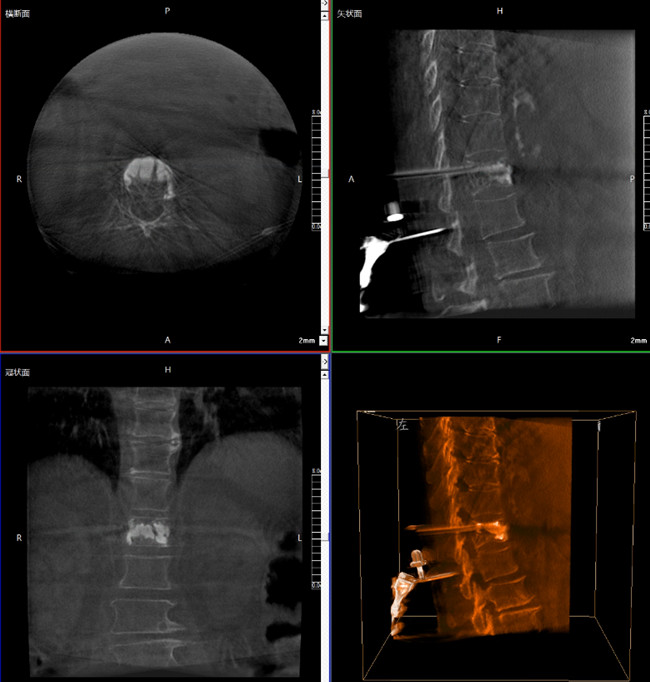

? 手术效果确认

*骨水泥置入效果良好

良好的临床使用体验源于普爱医疗骨科机器人导航系统和医生的完美配合。亚毫米级的准确定位、直观的术前规划和机械臂的执行,使医生无需扩大创口进行伤椎入针路径定位,仅需术前三维重建即可全方位了解伤椎位置及穿刺路径,除了极大的提高了一次性穿刺成功率,也大幅降低了手术对医生经验的要求,手术上手难度更低。